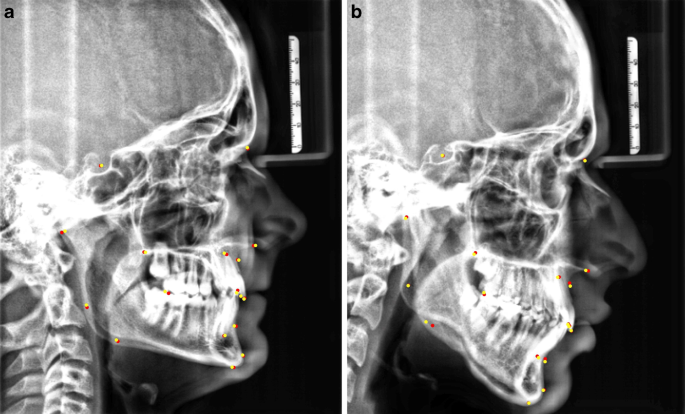

Validation images also pass the CNN algorithm: likewise, the mean absolute error is calculated in each epoch, but in contrast to training images, there is no further adjustment of the convolutional kernels of the CNN by error-calculation based feedback of validation images. The purpose of this procedure is comparison of error-calculation of training images versus validation images: after a certain number of epochs, the error-calculation of the validation images will not improve any further or possibly even worsen, whereas the error-calculation of the training images will probably further improve. This may be for example due to “overfitting” which describes a mere memorization of the training images by the CNN. An overfitted CNN will not achieve satisfying results for new and unexperienced images as it has lost ability to generalize. Therefore, the training status of the CNN with the lowest error-calculation for the validation images is set as final AI algorithm. At this point, the ability of the trained AI to precisely analyze completely new or unknown cephalometric X‑rays has to be clinically verified. Further improvement of the AI algorithm is only to be expected by adding new training samples and repeating the training procedure. Fig. 3 shows two examples of cephalometric X‑rays including the landmarks set by the AI as well as by the humans’ gold standard. These two examples were not part of the training data for the AI and therefore completely new to it.

Analysis of two cephalometric X‑rays previously unknown to the artificial intelligence (AI). AI (yellow) and the humans’ gold standard (red). a Cephalometric X‑ray of a patient with horizontal growth pattern. b Cephalometric X‑ray of a patient with vertical growth pattern and severe double contours at the mandible

Auswertung zweier für die Künstliche Intelligenz (KI) unbekannten Fernröntgenseitenbilder. KI (gelb), menschlicher Goldstandard (rot). a Fernröntgenseitenbild eines Patienten mit horizontalem Wachstumsmuster. b Fernröntgenseitenbild eines Patienten mit vertikalem Wachstumsmuster und starken Doppelkonturen im Bereich des Unterkiefers